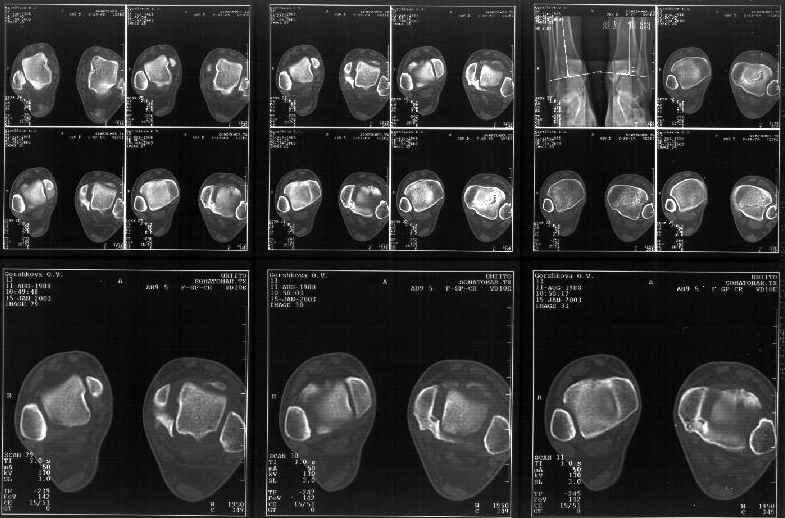

Сегодня пациентке сделали сравнительную КТ. А ксиальные и Фронтальные срезы приложены. Ваше мнение?

Фронтальные

Аксиальные

На КТ я попытался изобразить скромными своими способностями (А)- место перелома, (С)- нормальный суставной зазор меж тараном и тремя его маллеолами. (В)- образовавшийся в результате перелома широкий раза в три зазор, позволяющий, по-моему, сублюксацию тарана при ходьбе. В свете данных КТ, критически важных, я бы предложил вертикальную остеотомию места перелома

задне-внутренним подходом и фиксацию мед. маллеола прижатым к тарану с помощью тонкого compression screw. После этого гипсовый сапожок и немедленное расхаживание ноги.